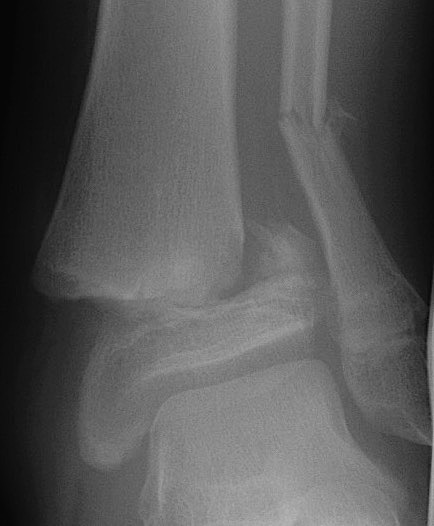

Triplanar Fracture

Definition

- fracture in coronal, sagittal and transverse planes

- 2, 3 or 4 part

Varieties

2 part

- can be medial or lateral based of site of main distal fragment

- typically anterolateral epiphysis attached to posterior metaphysis

- anteromedial intact distal tibia

3 part

- additional separate anterolateral epiphysis / Tillaux

4 part

- additional separate metaphyseal fragment

Xray

Type III / Tillaux on AP

Type II on lateral